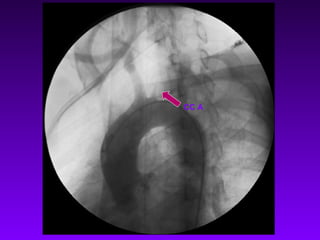

Catheterization and Angiography • Pan-aortography, preferably with intrarterial digital subtraction angiography most important diagnostic investigation helps in planning management Visualisation of entire Aorta& its major branches special attention to innominate, subclavian& extracranial portions of carotid arteries. • Coronary Angiography • Pulmonary Angiography

Rt CCA Long Stenosis Lt SCA Not Seen Rt SCA Narrowing